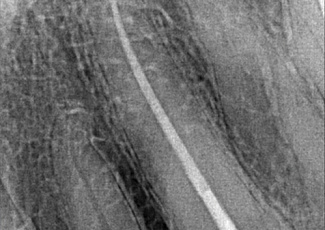

Під час другого візиту скарги у пацієнта були відсутні. Перевірили якість затвердіння силеру в усті кореневого каналу. Порожнину доступу закрили фотополімерним матеріалом.